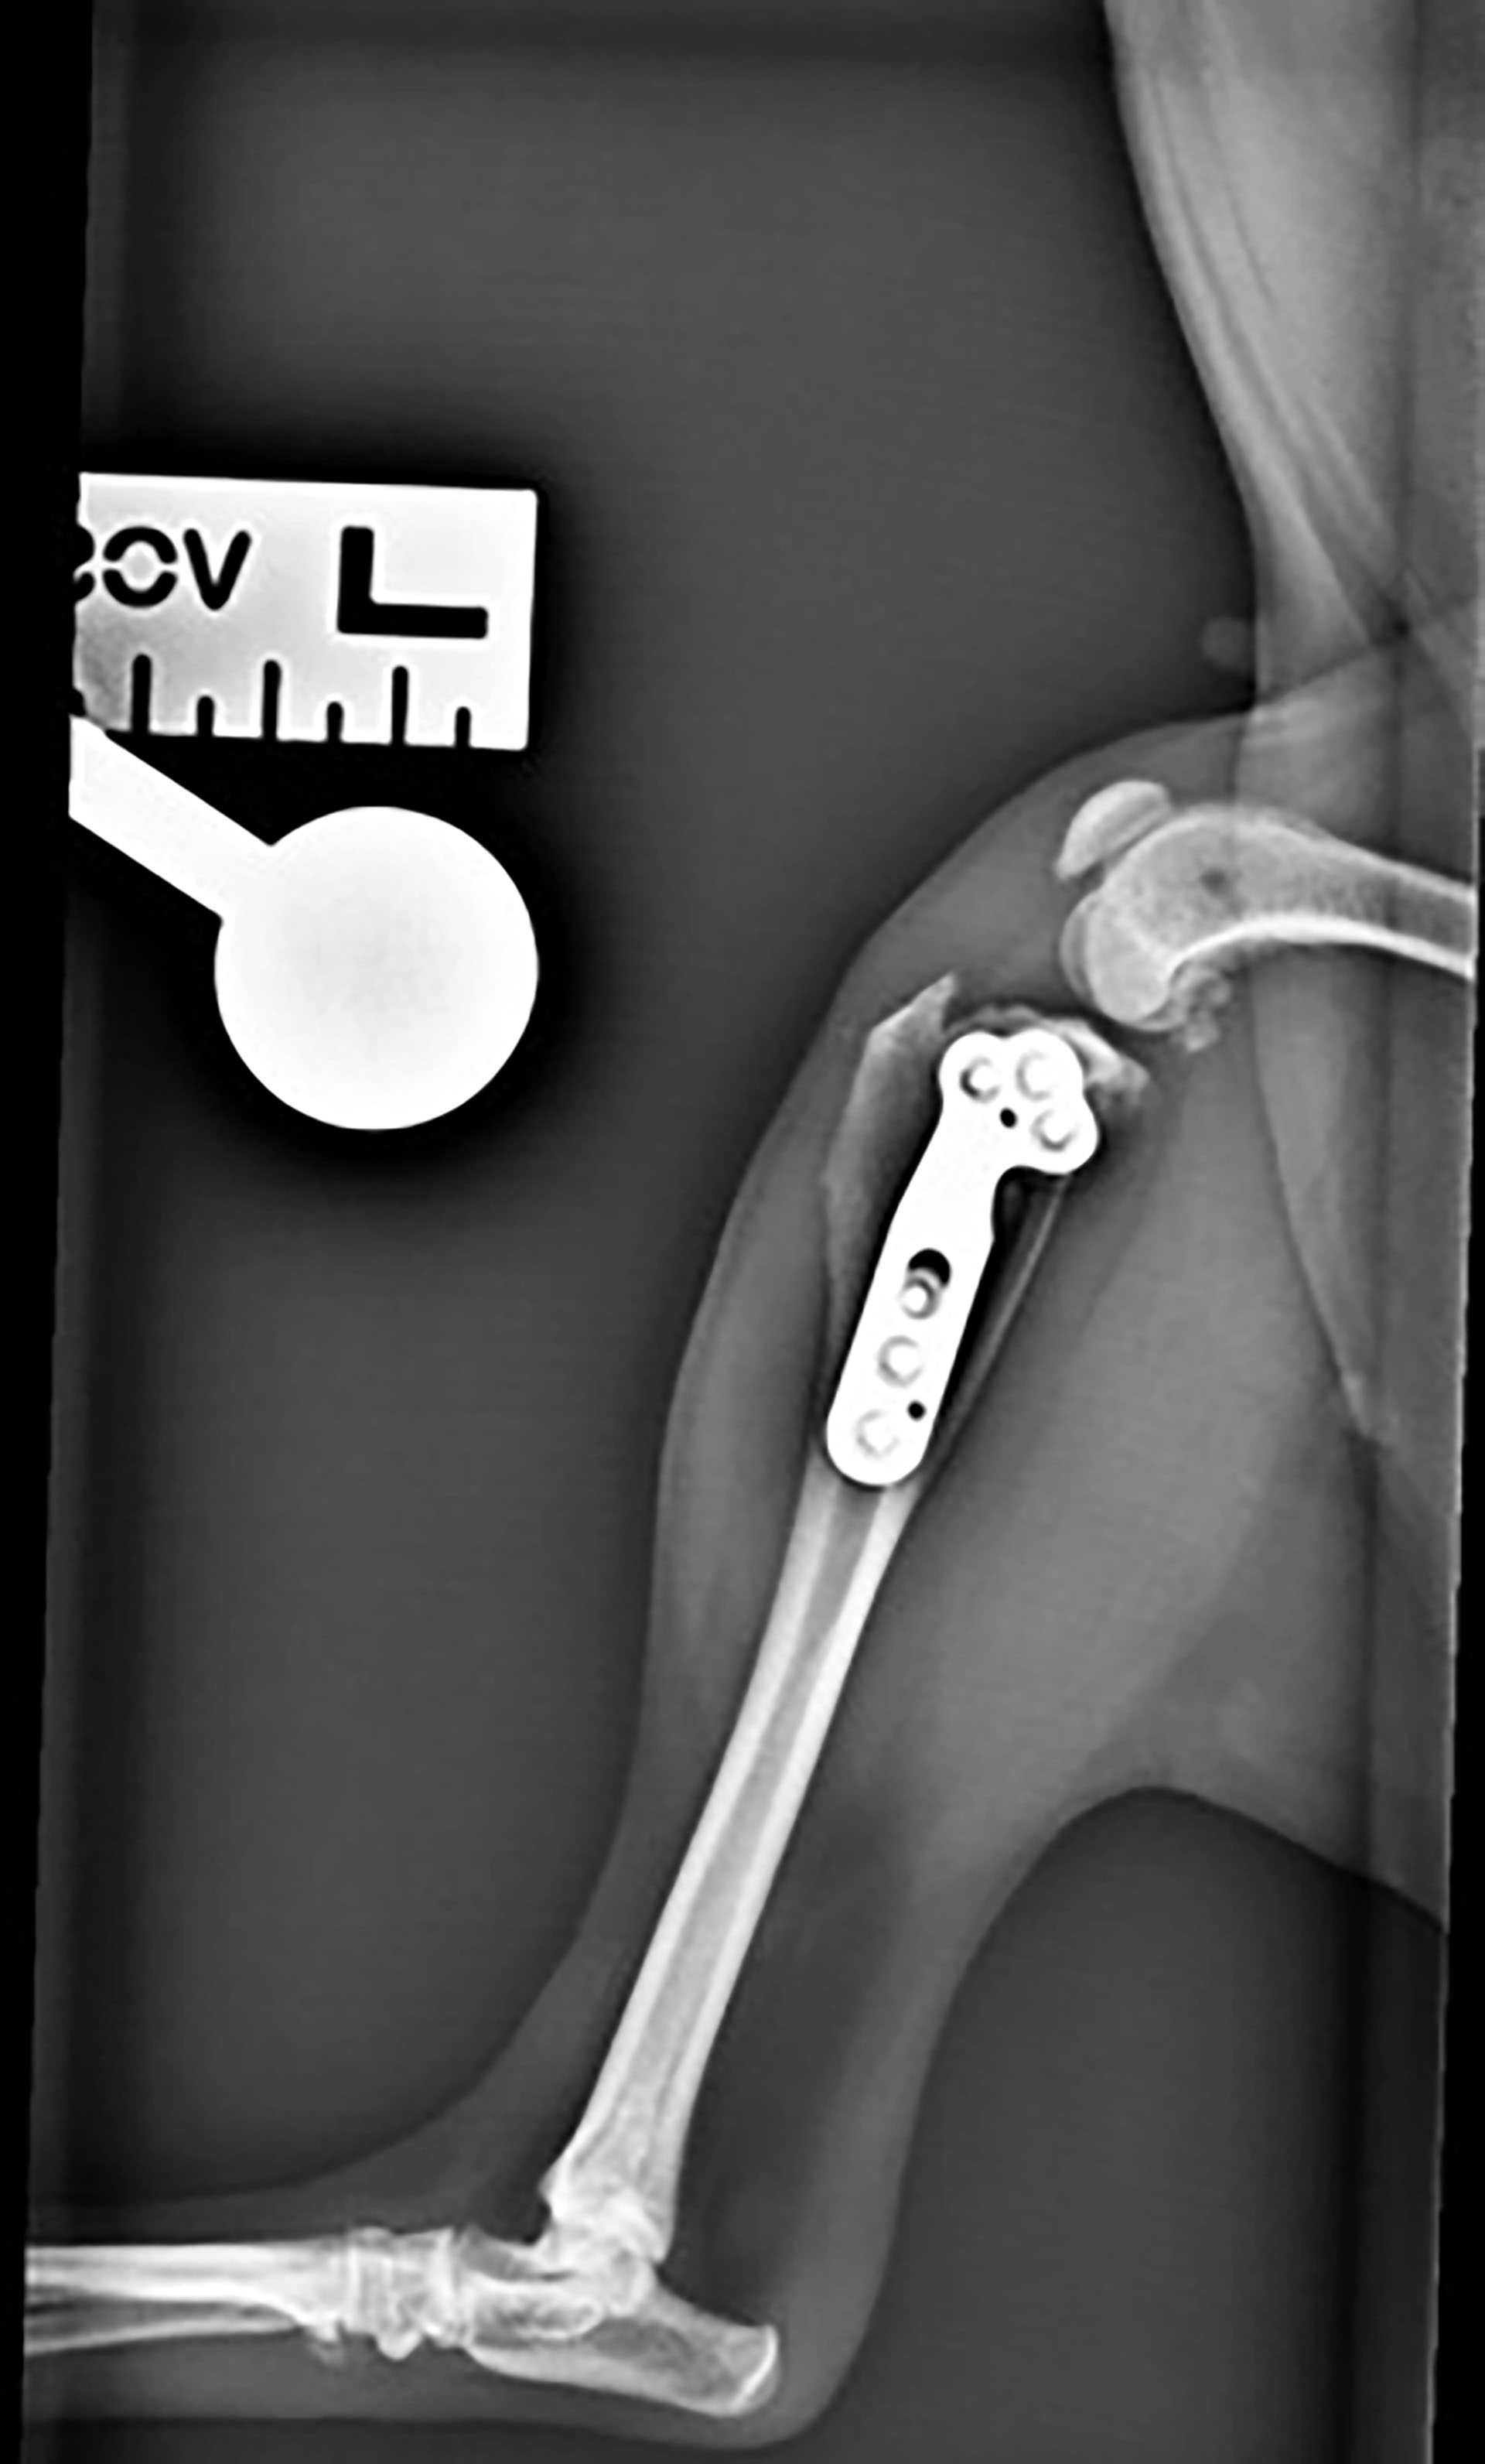

Sevofluranfordamper og ventilator ble skrudd av og pasienten pustet selv. Hunden ble ekstubert ved oppvåkning. Det ble gitt 1 mg/kg maropitant subkutant mot kvalme og 2 mg/kg robenakoksib subkutant mot smerte. Såret ble vasket og det ble lagt på et mepore plaster. Et fentanyl depotplaster 12 µg/time ble påsatt på høyre flanke. Det ble gitt fentanyl CRI etter operasjonen da plasteret ikke hadde effekt før etter 12 timer. Postoperativt ble det utført røntgenbilder av kneleddet (Figur 6 og 7).

Figur 6. Kraniokaudal projeksjon av kneledd postoperativt med plate og skruer.

Figur 7. Laterolateral projeksjon av venstre kne postoperativt.

Røntgenbildene viste tilfredsstillende resultat med TPA på fem grader. Det var tilfredsstillende osteotomiorientering, kompresjon, plateplassering og skruelengder. Hunden ble værende på hospitalet til dagen etter. Hun fikk fentanyl CRI i en rate på 3 µg/kg/time og intravenøs væske i form av ringer acetat 2 ml/kg/time. I løpet av natten ble fentanyl CRI titrert ned til 2 µg/kg/time. Hunden var i god form dagen etter operasjonen, spiste med god appetitt, og hadde en temperatur på 37,6 ˚C. Hun var respiratorisk og sirkulatorisk stabil og reiste hjem til eier denne dagen. Hun tok litt støtte på benet, og godtok å manipulere med det. Huden rundt operasjonssåret hadde mild erytem og mildt ødem. I tillegg til smerteplasteret hun hadde på seg fikk hun også robenakoksib 1 mg/kg (totalt 10 mg) som ble gitt per os en gang daglig i fire uker. 14 mg/kg gabapentin per os to ganger daglig ble gitt som ekstra smertelindring den første uken. Det ble satt opp kontroll med stingfjerning 14 dager etter operasjonen, og røntgenkontroll var planlagt seks uker etter operasjonen. Hunden ble holdt i ro frem til røntgenkontrollen. Fentanylplasteret ble fjernet tre dager senere.